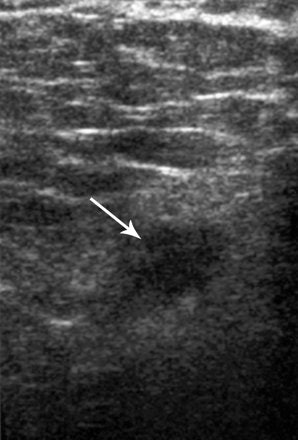

A subsequent ultrasound exam revealed an ill-defined, hypoechoic mass. A histopathological exam of a biopsy sample "revealed a polymorphous infiltrate of histiocytes … with round nuclei (that) expressed S-100 protein, characteristic of Rosai-Dorfman disease," wrote Dr. Cynthia Pham and colleagues (American Journal of Roentgenology, October 2005, Vol. 185:2, pp. 971-972).

| Fifty-three-year-old woman with Rosai-Dorfman disease of the breast. Above, left breast craniocaudal mammogram shows 1.5-cm high-density mass with indistinct margins (arrow). Below, left breast longitudinal sonogram shows ill-defined, hyopechoic mass. Pham CB, Abruzzo LV, Cook E, Whitman GJ, Stephens TW, "Rosai-Dorfman Disease of the Breast" (AJR 2005;185:971-972). |

The patient was ultimately diagnosed by ultrasound-guided needle core biopsy followed by stereotactic vacuum-assisted core biopsy, the authors stated, adding that surgery was unnecessary.